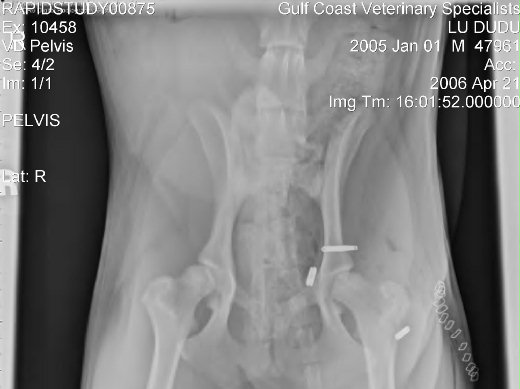

嘟嘟到了急診室,護士給牠洗個澡,傷處剃除部分狗毛,前後肢各照了兩張X光,確定除兩處骨折外,沒有內傷及生命危險。因為小醫院無法動骨科手術,次日只好出院,花費八百大洋。

醫師看了X光片,和我們討論嘟嘟的傷勢:左前肢呎骨雙雙斷裂,要以支架固定,比較簡單。左臀部大腿骨關節錯位,並且部分磨傷,需以鋼釘穿過關節並在兩頭固定之。手術要等第三天才排到嘟嘟,再休息兩天才出院,先付一半費用約2,500美元,出院時再付餘款。

不多久, 和藹可親的Beals醫生來到,以開刀後的X光片,與我們顯示完成手術細節及交待注意事項,護士小姐並給了兩小瓶分別是抗生素及止痛藥帶回給嘟嘟按時服用。兩周後再回診,完全痊癒需時兩個月,屆時還要再照X光(約$150~200元)以確認康復。